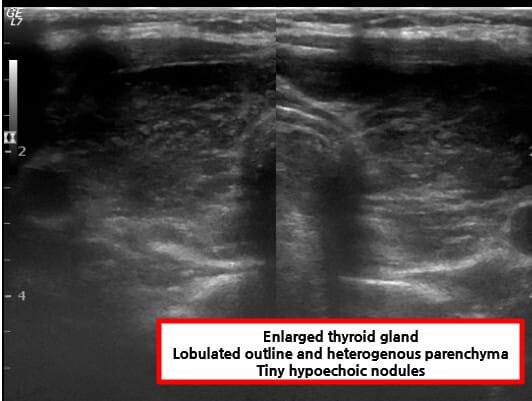

영상 검사 소견

| 영상검사 소견 (초음파) |

| – 갑상선 초음파에서 저에코성 변화 |

| 염증과 섬유화로 인해 정상 조직보다 음파 반사가 적어 저에코성(hypoechoic)으로 보입니다. |

| – 갑상선 크기 불균일 및 결절성 변화 |

| 만성 염증으로 갑상선 조직이 불규칙하게 섬유화되고 결절성 변화를 일으켜 크기가 균일하지 않게 보입니다. |

| – 혈류량 감소 또는 불규칙한 혈류 패턴 |

| 만성 염증과 조직 파괴로 인해 정상적인 혈류가 줄어들거나 혈류 분포가 불규칙하게 나타납니다. |